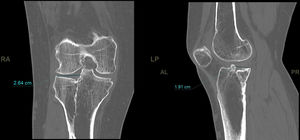

En la telemetría se analizó la desviación en mm del eje de carga respecto al miembro contralateral, el medial proximal tibial angle [MPTA) de ambos miembros y la diferencia en grados entre ellos (fig. 2).

En el análisis de la telerradiografía la diferencia de la desviación media del eje con respecto a la pierna contralateral fue de 12mm. La diferencia media del MPTA fue de −1,1grados.